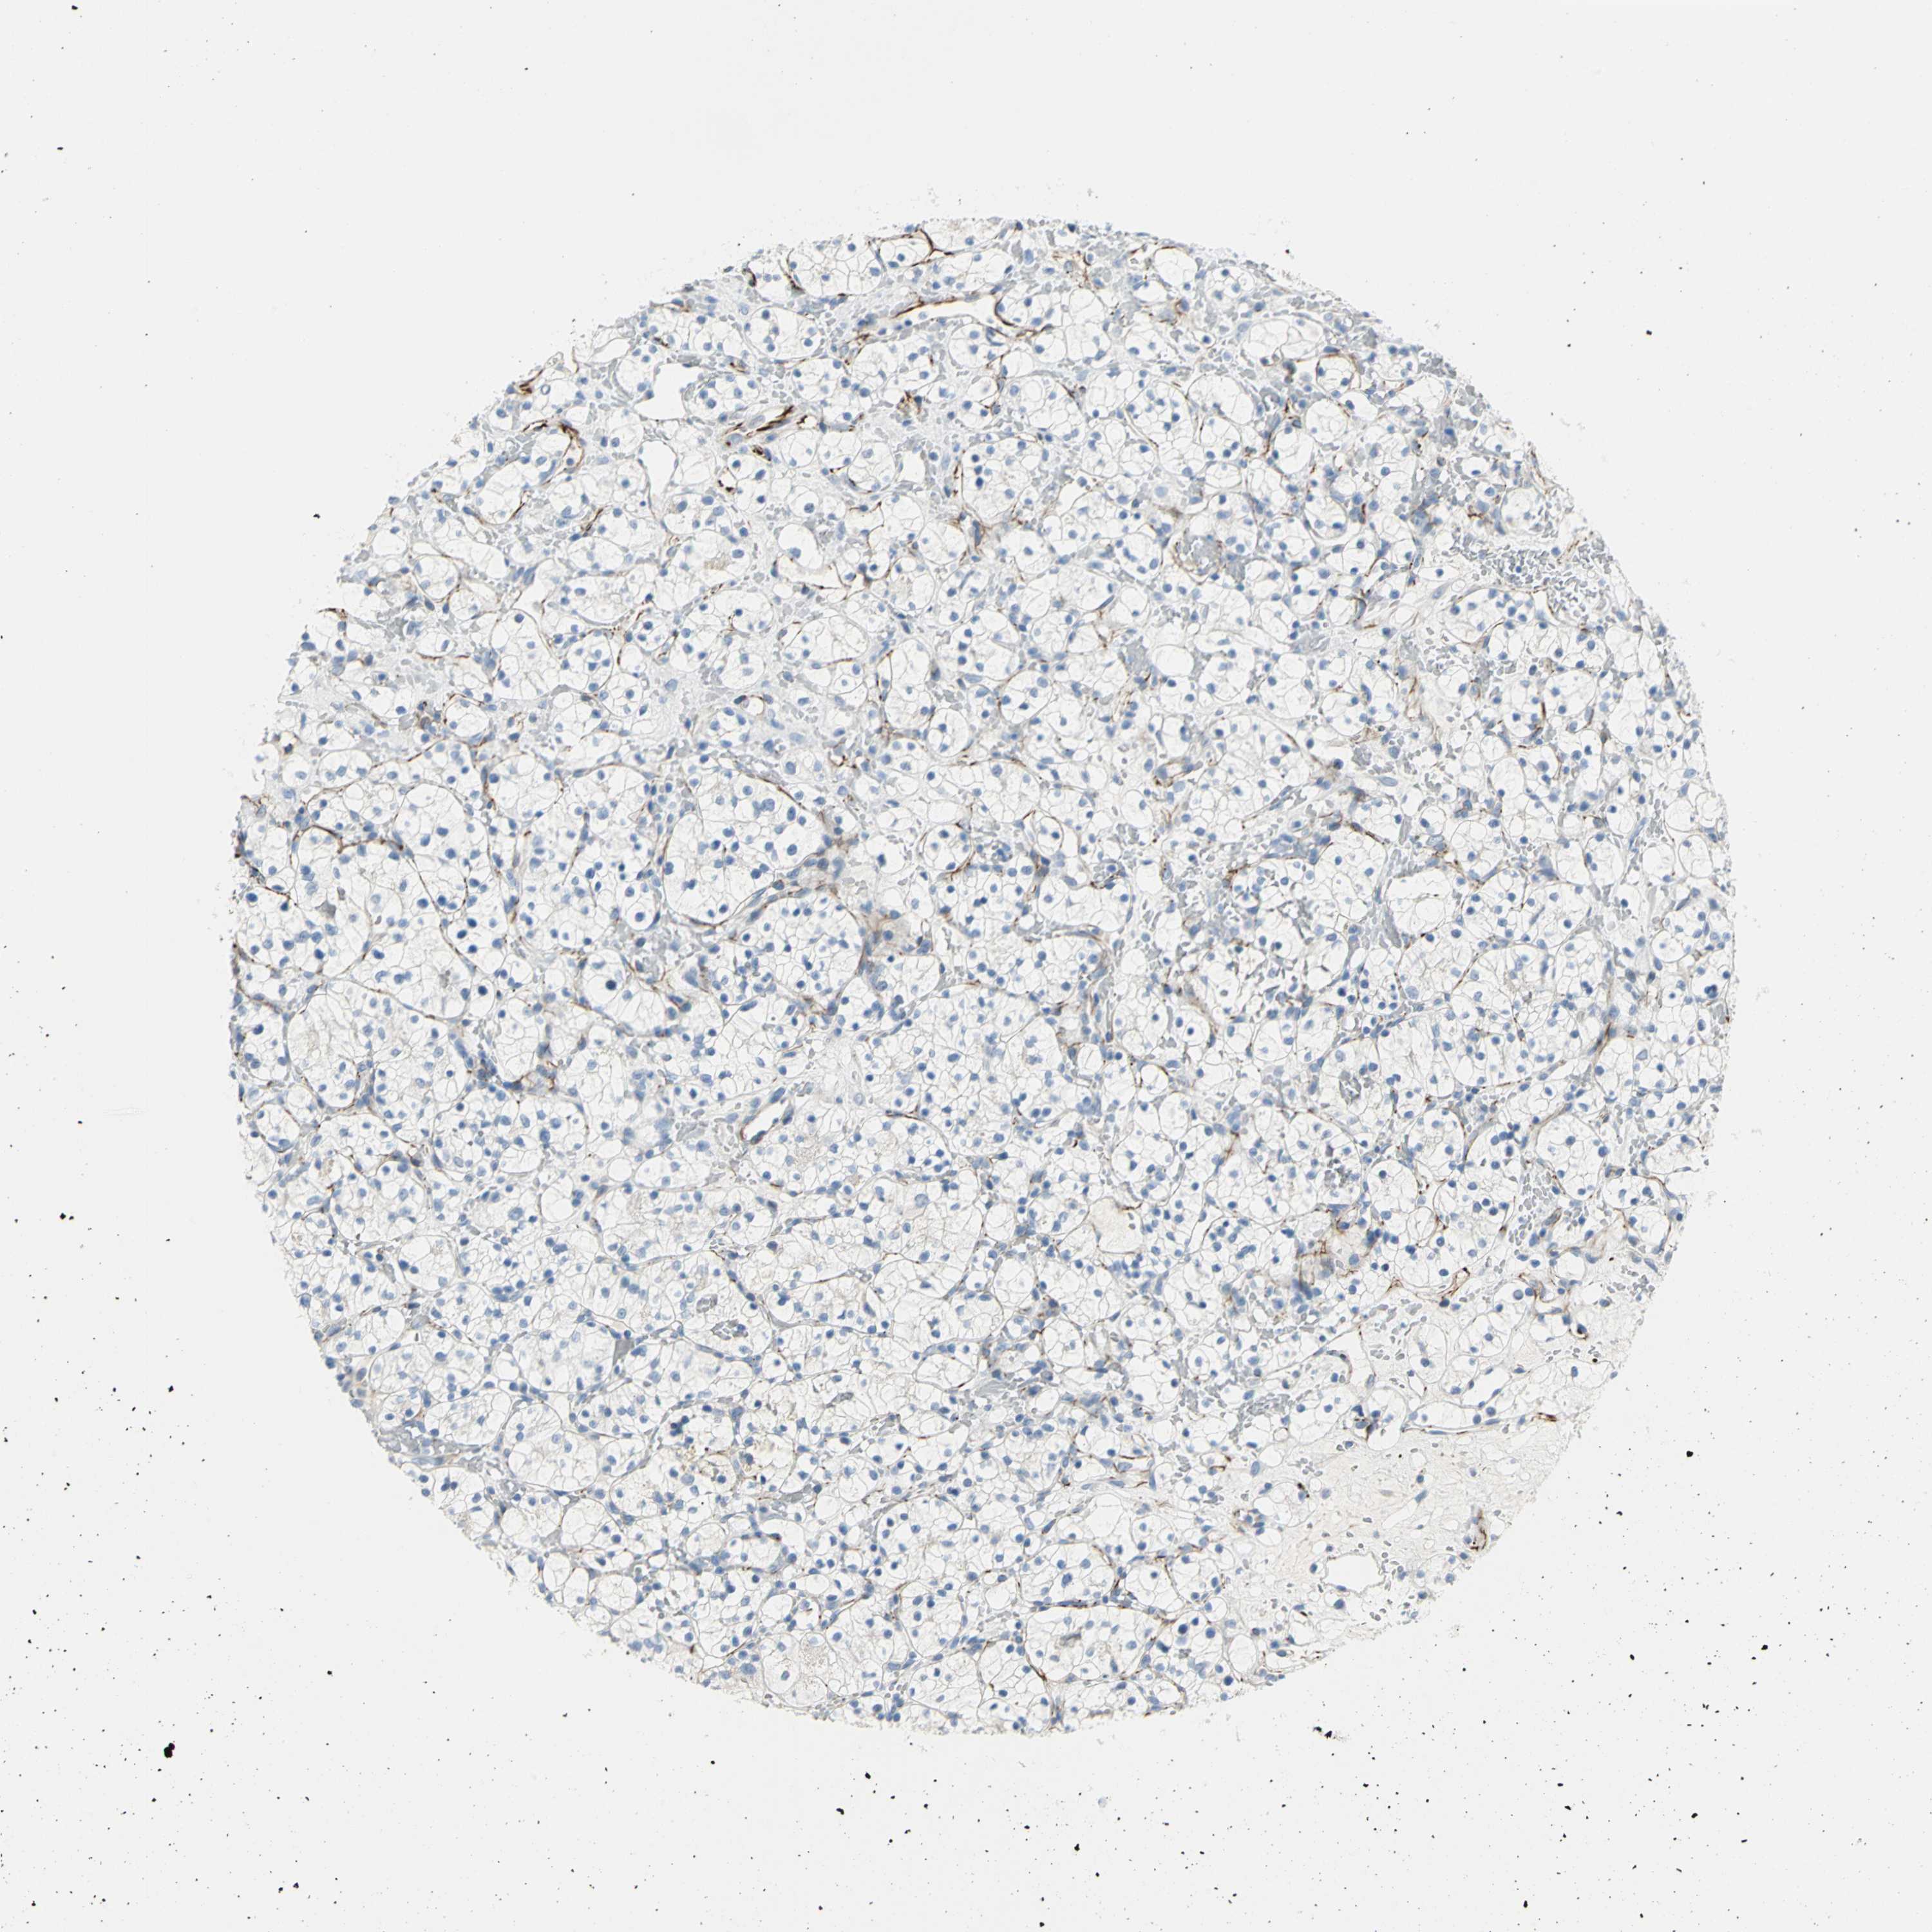

CANCER RENAL CANCER Show tissue menu

KICH TCGA KIRC TCGA KIRC VALIDATION KIRP TCGA PROTEIN RCC CPTAC PROTEIN EXPRESSION